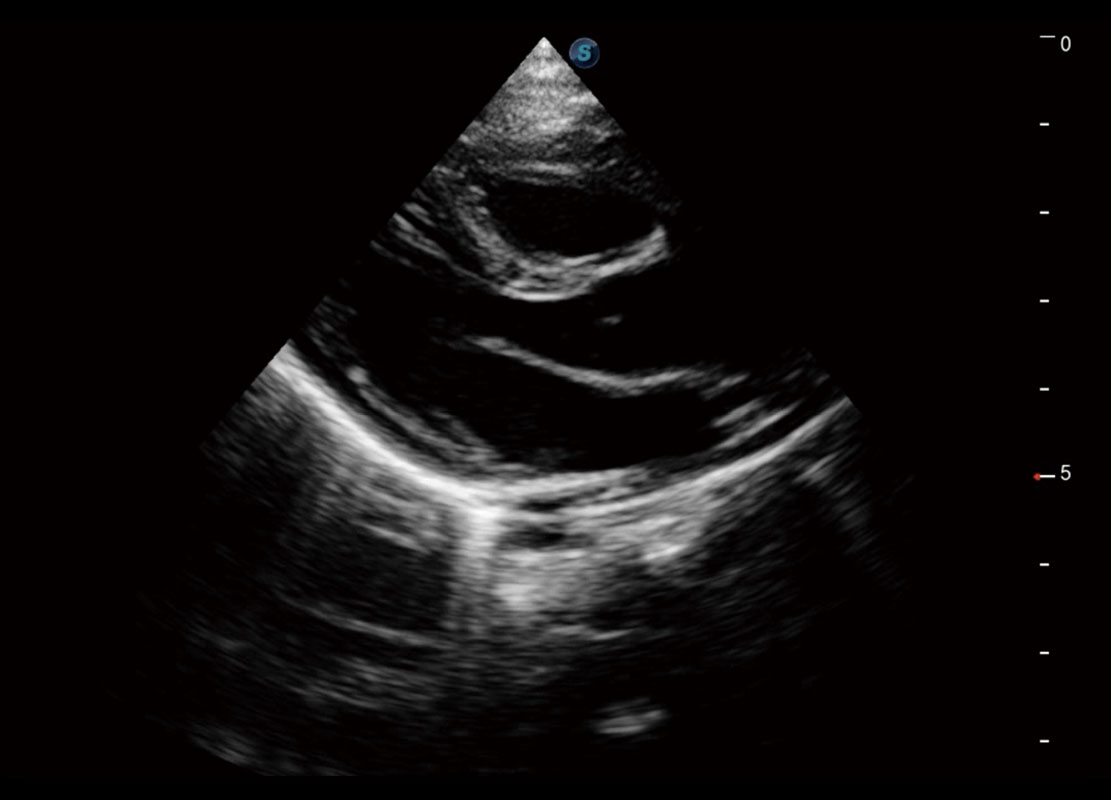

P60搭载一系列胎儿心脏成像技术,实现精细的胎儿心脏评估。

四腔心血流

右室双出口